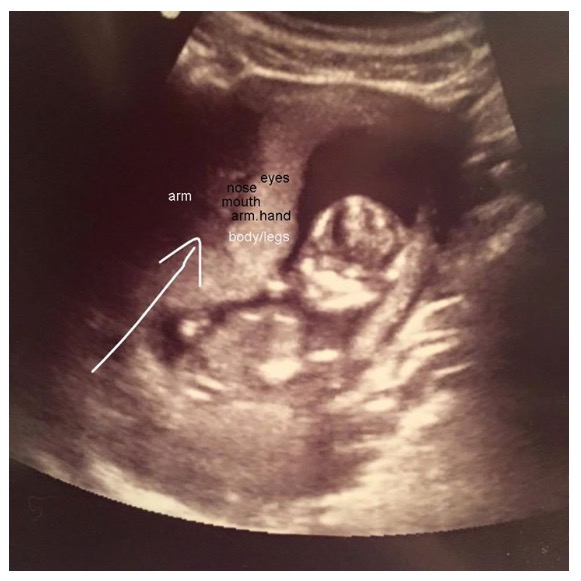

Surprised with identical twins at my 12 week ultrasound! r/BabyBumps Ultrasound Pictures Of Hidden Twins How common are hidden twins, and what clues can you look for? 6 week ultrasound | nerves, pictures and twins. During the early stages of pregnancy, an ultrasound may reveal a hidden twin. By sam mcculloch dip cbed. Just found out you’re pregnant and are having (or had!) an ultrasound? You probably have lots of questions about early pregnancy ultrasounds.. Ultrasound Pictures Of Hidden Twins.